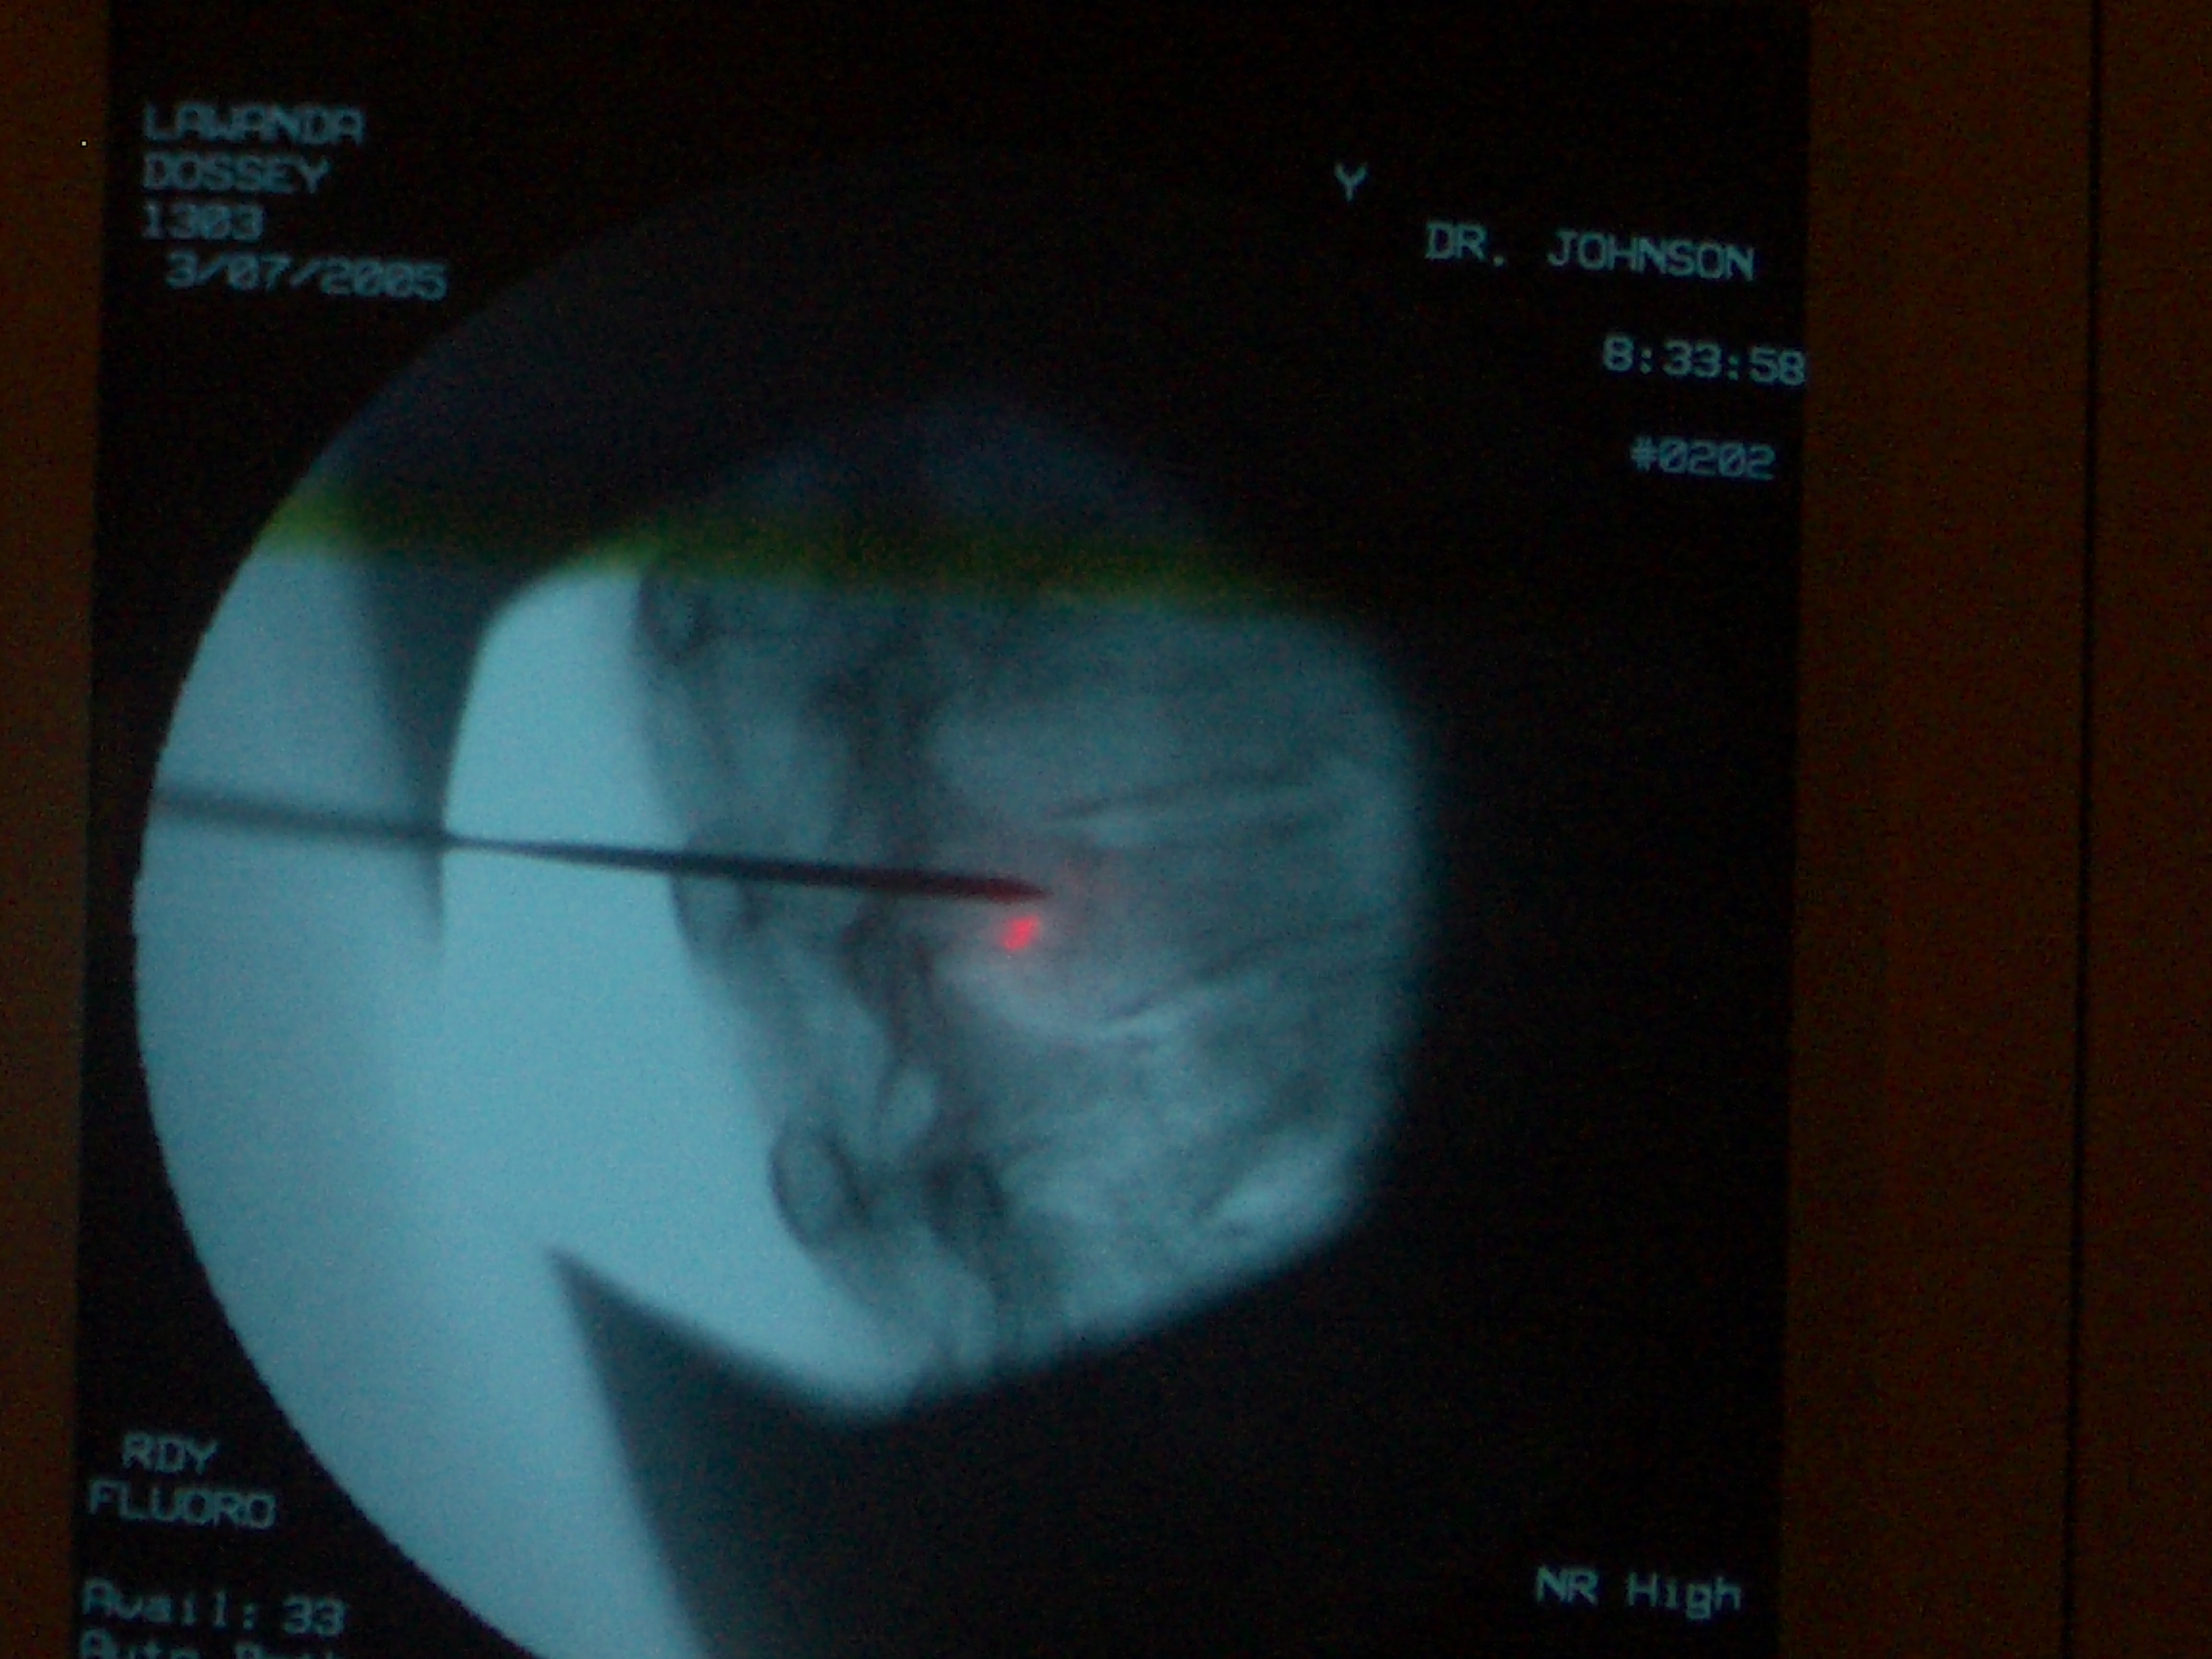

Vertebroplasty fluoro